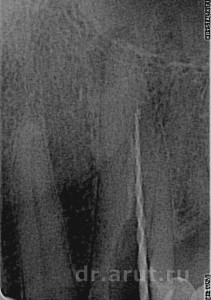

10 дней спустя, при обследовании во время повторного приёма выяснили, что перкуссия безболезненная, жалоб на боли нет. Удалили временную пломбу, провели повторную медикаментозную обработку канала парканом и 3% перекисью водорода. Канал высушили и запломбировали силером с гуттаперчиевым штифтом методом вертикальной конденсации.

- Запломбированный канал на всю длину

- Пломбирование канала силером с гуттаперчей